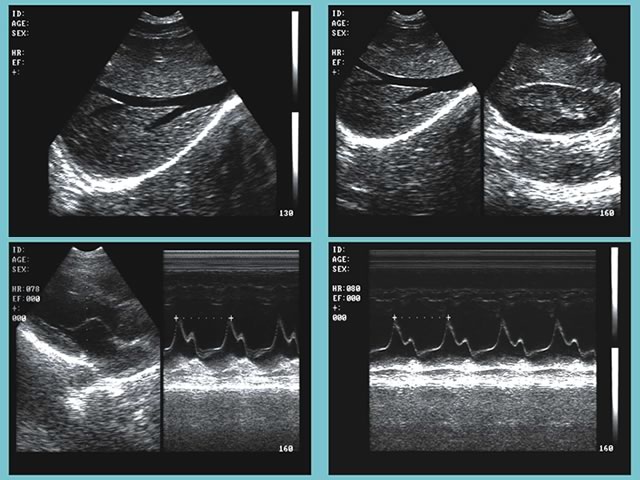

超聲診斷在醫學臨床上已使用多年。超聲波被廣泛使用,因為其易于使用且價格比其他成像方法便宜。一家大型美國診所在16個房間內提供各種各樣的超聲波檢查。 Epiphan VGA Grid有助于超聲檢查人員在空中與相關專家進行溝通

VGA Grid通過VGA圖像采集卡(Epiphan VGA2Ethernet)與安裝在每個檢查室中的最頂尖的超聲波設備相連接。VGA圖像采集卡捕捉來自設備的信號,并通過以太網發送至VGA Grid。它可以同時捕捉和記錄帶有時間戳的所有會話。進行檢查的超聲醫師在其得出結論前,可能需要與專家進行討論。完成成像后,檢查室專家可能有問題需要與主治醫生、主管或其他受過專業醫療成像培訓的專家進行討論。

超聲視頻可以在需要時進行重放或縮小。無論專家們在哪里,他們都能夠查看來自多個來源的視頻。他們通過網絡接口訪問超聲波圖像(錄制或直播)。根據研究結果,他們判斷進一步的研究是否會有幫助,然后做報告,并告知病人結果。 VGA Grid使一次性查看來自多個檢查室的超聲設備信息成為可能,中央控制中心就能監測到哪間房間是可用的。高端的設備可以使門診超聲檢查師立即獲得診斷信息,更有效地治療患者。